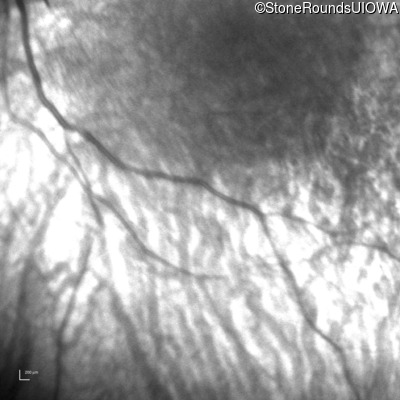

Infrared Fundus Photograph - Right -

Light Perception

Exemplar

Infrared Fundus Photograph - Left -